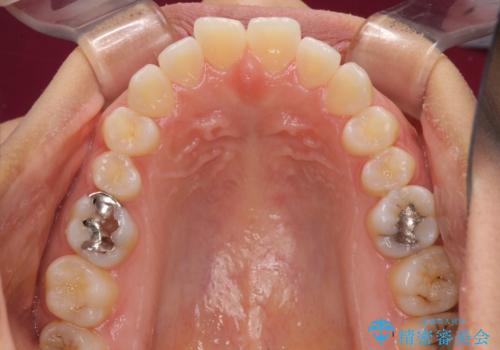

受け口傾向の前歯 すきっ歯の改善

- 前歯の隙間と口元の突出感を気にして来院された患者様です。

嚥下時に舌を突出させる癖があり、成長期に下顎が有意に成長し、歯と歯の間に隙間ができてしまいました。

舌の癖を改善し、インビザラインにて治療を行うこととしました。

舌癖を改善したことで、隙間や突出感を改善することができました。

隙間は後戻りしやすいため、舌側を細いワイヤーで固定することとしました。